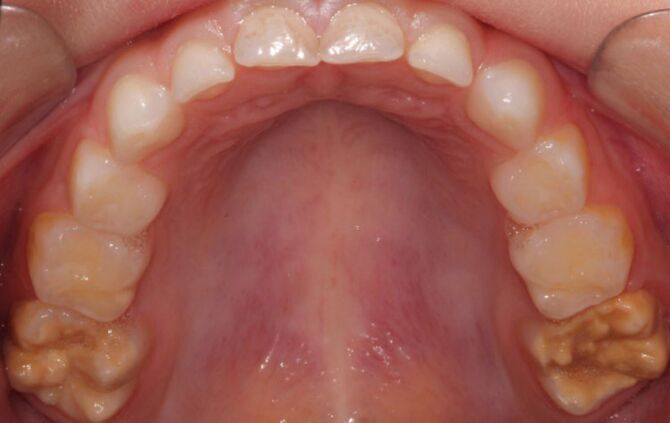

Kreidezähne haben oft gelblich-bräunliche Verfärbungen. © privat